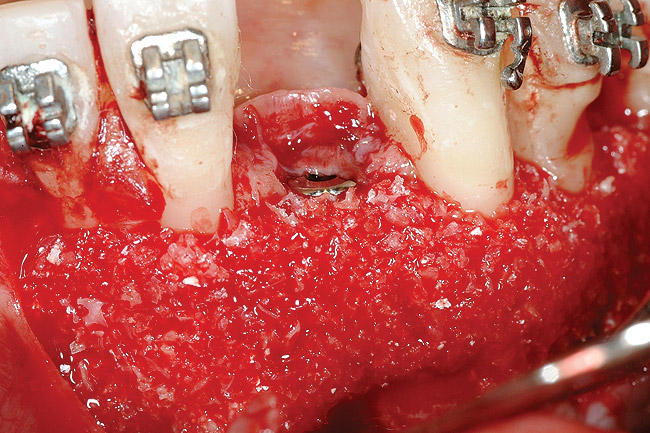

Figure 19  Mineralized freeze-dried bone allograft hydrated with platelet-derived growth factor covering root dehiscences and implant dehiscence.

Figure 19

Figure 20  Tension-free primary wound closure.

Figure 20